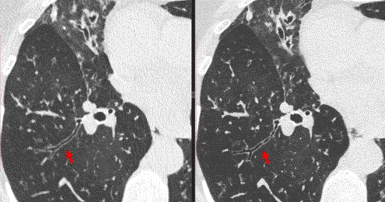

Photon Detector Breathes New Life Into Conventional CT Imaging

The Food and Drug Administration has cleared a photon-counting detector (PCD)-based CT system for clinical use. The system offers an alternative approach to the conversion of x-rays to electrical signals. Studies also showed that the system achieved the best reported resolution for a clinical CT system.